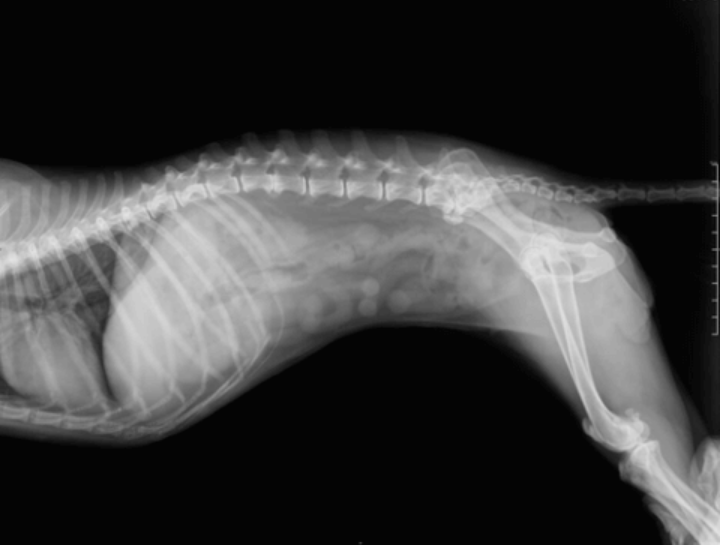

Pet Digital Radiology

Medical Imaging for Pets